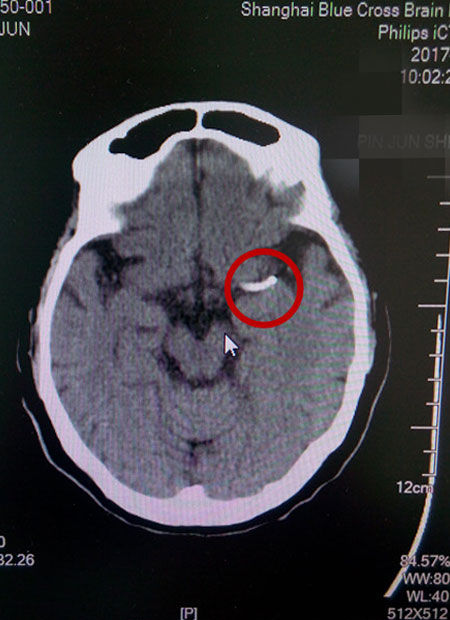

術(shù)后CT影像:支架成功置入

就這樣,這臺DSA手術(shù)又一次獲得了成功,術(shù)后CT復(fù)查無出血,患者恢復(fù)情況良好,這才出現(xiàn)了本文開頭的感人一幕。原本大面積腦梗、病情兇險的的盛阿姨在李主任和團(tuán)隊的努力下,通過DSA球囊擴(kuò)張支架置入術(shù),平安度過了生命中的一個轉(zhuǎn)折點(diǎn)。隨后,在不到一個月的時間里,她的語言功能已逐漸恢復(fù),四肢肌力已經(jīng)接近正常水平,目前正在積極接受康復(fù)治療中。